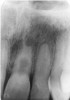

Elongation

Description: A radiograph is a two-dimensional representation of a three-dimensional object. Incorrect positioning of the tubehead’s central ray relative to the object to be radiographed results in a distorted image. If the central ray of the tubehead is placed at too shallow a vertical angle relative to the long axis of the teeth, and thus is not perpendicular to the long axis for paralleling technique or the bisector (90º angle) in the bisecting angle technique, the crown and root images will appear long (Figure 3).

Differential Diagnosis: If vertical beam angulation is too shallow, the entire tooth and roots will appear elongated. If film bending was at fault, the roots will generally be elongated, but the crown will appear normal.

Consequences: The image may still be acceptable, despite the error. If the elongation interferes with the film’s diagnostic quality, a retake is necessary.

Remedy: The operator should review technical procedures regarding vertical angulation in relation to either Paralleling or Bisecting technique, and repeat the film. The operator should increase the vertical angulation in order to correct elongation of an image.

Figure 3. Elongation.

Figure 3